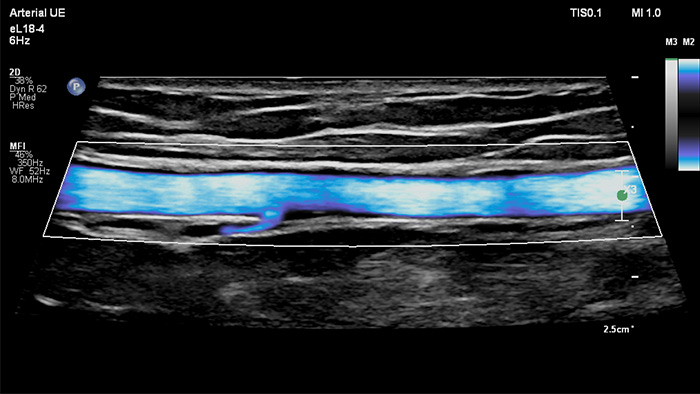

Philips MicroFlow Imaging wurde für die Erkennung langsamer und schwacher Blutflüsse in Gewebe entwickelt und verbessert bei Gefässuntersuchungen die Flussauflösung mit beeindruckender Empfindlichkeit. Subtile, pathologische Strömungsverhältnisse um stenotische Plaques lassen sich durch die hohe Auflösung und minimale Artefakte visualisieren und charakterisieren, was die Diagnosesicherheit unterstützt.